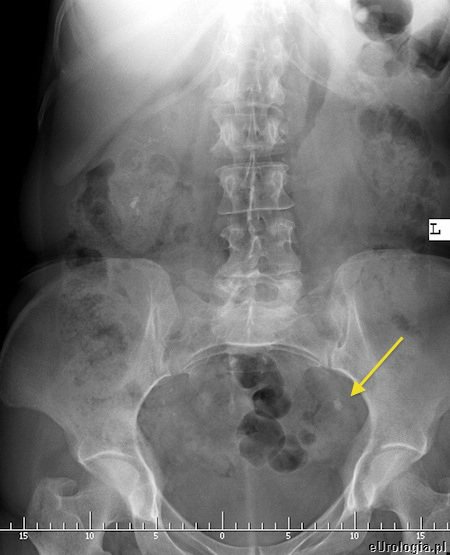

Ustalenie lokalizacji złogu w moczowodzie czasami bywa trudne w warunkach ambulatoryjnych. W przypadku podmiedniczkowego i śródściennego odcinka moczowodu czasami udaje się uwidocznić złóg w czasie USG jamy brzusznej. Złogi uwapnione w większości przypadków widoczne są na zdjęciu przeglądowym jamy brzusznej. Aby dokładnie uwidocznić kamień i ustalić czy cienie mogące być uwapnionymi złogami na zdjęciu zlokalizowane są w moczowdzie należy wykonać urografię lub tomografię komputerową. Czasami konieczne jest ustalenie lokalizacji złogu wykorzystując pielografię zstępującą - u pacjentów z przetoką nerkową - nefrostomią lub pielografię wstępującą.

Fot. Zdjęcia przeglądowe jamy brzusznej pacjentów z kamicą moczowodową. strzałkami zaznaczono złogi w moczowodach.